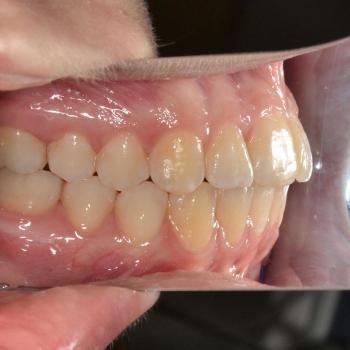

Eszter és édesanyja az iskolai fogorvosuk javaslatára kerestek fel, mert a kolléga, az esztétikai problémát okozó torlódás mellett, Angle II. osztályú funkciós eltérést is tapasztalt. Szerencsére ezeken felül egyéb eltérésre a konzultáció alkalmával sem derült fény.

Eszter a kezelés megkezdésekor headgear típusú fogszabályozó készüléket kapott annak érdekében, hogy a felső nagyőrlőket hátrafelé mozgassuk, illetve, hogy a keletkező rést felhasználjuk a kisőrlők és a szemfogak hátramozdítására is. Az így felszabadult hely az Eszter által választott hagyományos fém fogszabályozó segítségével felhasználható volt a metszőfogak elrendezéséhez, azok túlzott előredőlése nélkül.

A kezelés eredményeként minden kiindulási problémát sikerült megoldani és egy esztétikailag és funkcionálisan is szép mosolyt létrehoznunk.